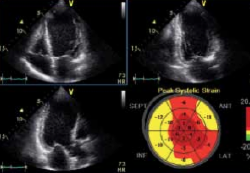

心臓超音波画像診断は収縮能が主な診断材料でしたが、近年では拡張能も超音波心機能指標として重要となり、多くのシーンで活用されています。さらに収縮能をより定量化する手法も一般化されつつあり、動いている心臓を簡便にリアルタイムに見る事の出来る唯一の重要な検査です。